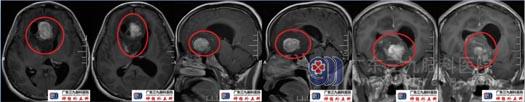

术前头颅MRI示右侧额颞叶、右侧基底节区、透明隔区及左侧额叶示一团块状不均匀长T1、长T2异常信号影,Flair序列呈高信号,间杂囊状明显长T1、长T2异常信号影,范围约62mm×56mm×43mm,增强后病变局部片状、斑片状、环状不均匀异常强化,周围示斑片状Flair序列高信号水肿影,累及胼胝体压部,视交叉、右侧大脑脚、右侧侧脑室前角、第三脑室、双侧侧脑室室间孔不同程度受压。ASL:右侧额颞叶、右侧基底节区、透明隔区及左侧额叶团块状病灶变低-稍高灌注;DTT(白质纤维束三维重建)右侧额颞叶、透明隔区及左侧额叶团块状病灶内纤维紊乱、中断;右侧皮质脊髓束显示稍稀少;双侧枕额束前份、右侧扣带束显示稀少;胼胝体束显示紊乱,请结合临床。影像学诊断:右侧额颞叶、右侧基底节区、透明隔区及左侧额叶占位性病变,考虑偏高级别成人弥漫性胶质瘤。